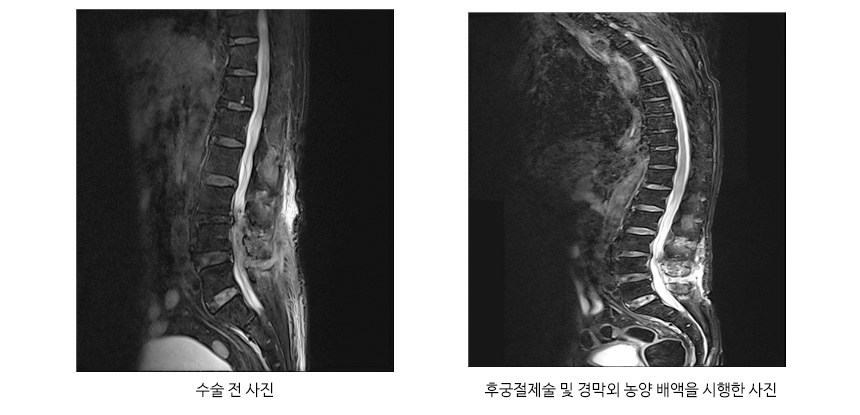

보존적 치료인 약물요법, 물리치료를 시행하여 진행상태를 확인하고 마비, 뼈의 불안정성, 통증이 계속 유발되는 경우 감압후궁절제술, 후궁절제술 등을 시행합니다.

세균성 척수염

결핵성 척수염